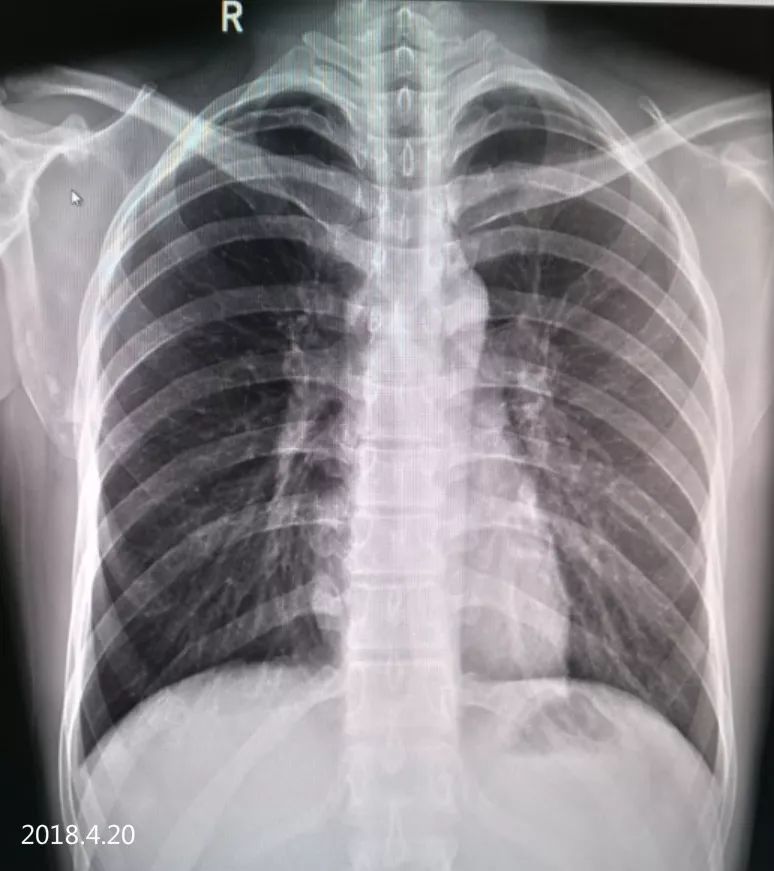

2018.4.17 气胸复张,右下肺见液平面已吸收

2018.4.20 经过约20天的治疗,肺组织已复张